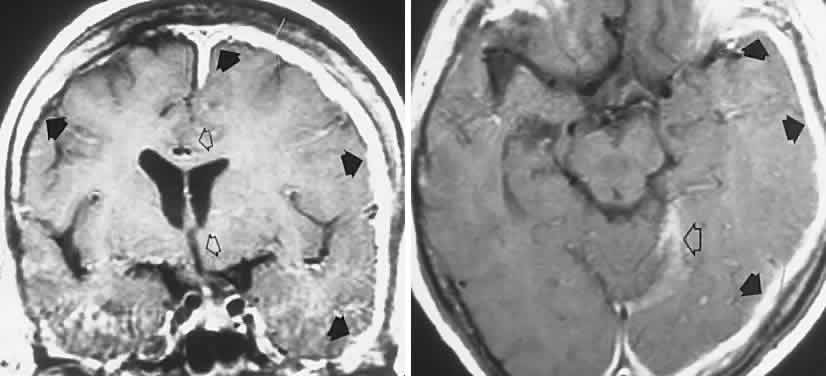

The spectrum of ocular, orbital, and CNS involvement with human immunodeficiency virus (HIV) infection, and subsequent acquired immune deficiency syndrome (AIDS), is vast and complicated, characterized by peculiar neoplasia and a host of opportunistic infectious agents that invade the retina, optic nerve, leptomeninges, and brain, at times mimicking other neurologic syndromes. Co-existing manifestations in the eye and brain present confounding factors for neuro-ophthalmologic localization. The usual parsimonious medical expectation that a single basic disorder encompasses all manifestations of an illness is inoperative in the patient with severely depressed cellular immunity, and, indeed, unrelated problems may be mislabeled. Ocular findings are detected in the majority of patients with AIDS at sometime in the course of the disease, the most common being relatively asymptomatic noninfectious microangiopathy consisting principally of microinfarcts (“cotton-wool spots”) admixed with small hemorrhages, occurring in at least 50% of patients with AIDS, 34% of those with AIDS-related complex, and 3% of persons with asymptomatic HIV infection.123 Interestingly, there is distinct evidence124 of abnormal visual function (contrast sensitivity function, automated perimetry, color sense) in HIV-positive patients without ophthalmoscopic evidence of retinopathy, with normal global neuropsychologic function, and unrelated to disease state as determined by markers including CD4 T-lymphocyte count. It is speculated that such visual function may be related to HIV infection at some level of the visual pathways, or it may be an effect of antiviral or other therapeutic agents. Morphometric techniques125 have demonstrated markedly lower mean axonal populations in AIDS-affected optic nerves, possibly reflecting a form of primary optic neuropathy (see Part II of this chapter for discussion of optic neuropathies in AIDS).

Opportunistic infections, particularly CMV retinitis, are major causes of severe visual loss and blindness; CMV retinitis is estimated to occur in 37% of patients with AIDS.126 CMV retinitis is a relatively late manifestation of the basic disease and is associated with CD4 T-cell counts of less than 0.10 × 109/L. Other tissues are affected, including the brain, lungs, and gastrointestinal tract. CMV retinitis presents as patches of opaque retina with intraretinal hemorrhages and exudative borders of advancing necrosis, which may eventuate in retinal detachment. Intravenous or intraocular ganciclovir and intravenous foscarnet are effective in controlling (viro-static) CMV retinitis, but they do not eliminate the virus.126